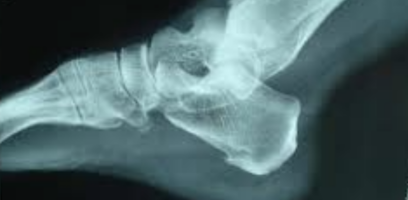

足底筋膜炎是引起足跟痛的最常见病因之一。足底筋膜炎是一个医学术语,医生用它来描述足部“跖腱膜”的炎症。跖腱膜是连接跟骨和趾骨的坚韧带状组织。(如图1)

结合症状和进行体格检查,医生应该能判断您是否患有此病。他们可能建议进行X线检查(图2)或肌肉骨骼超声检查,同时配合足底压力测试检查。

图2:足X线提示跟骨骨刺形成